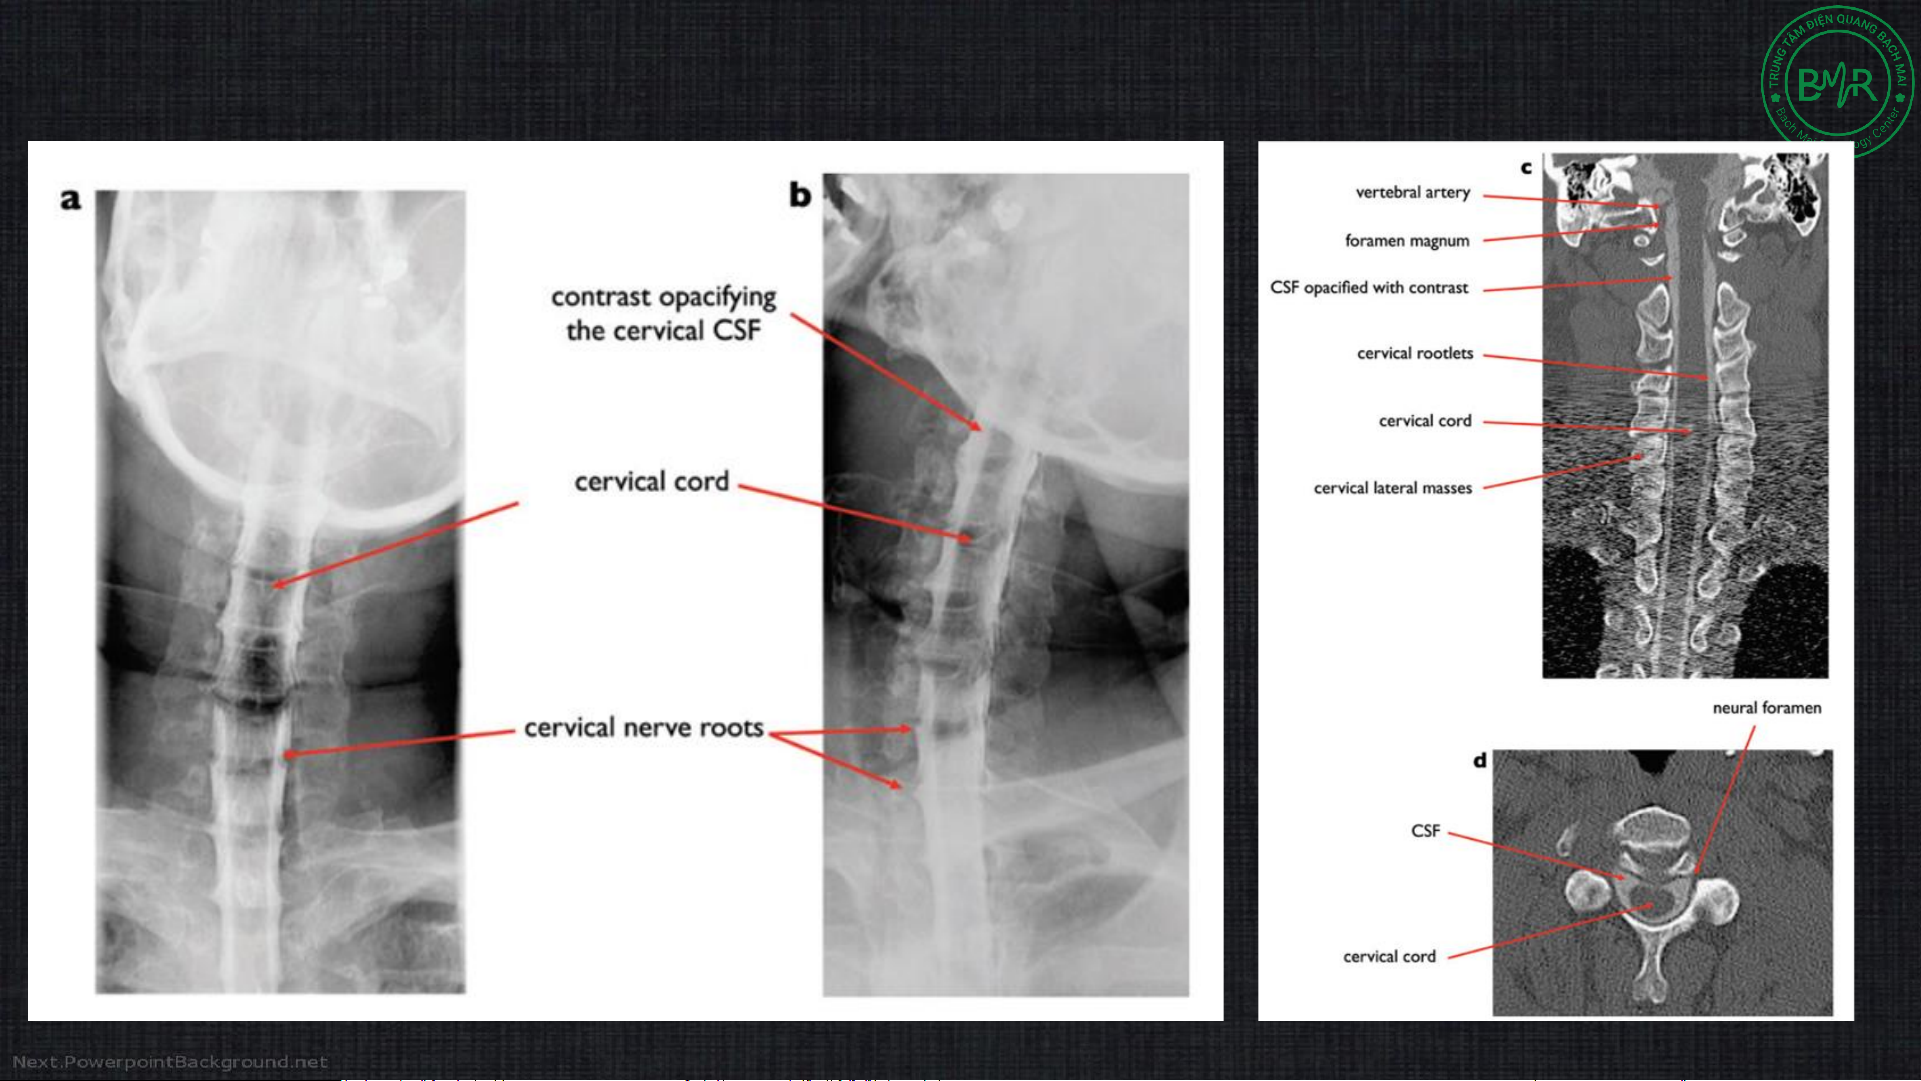

2c. Chụp tủy sống (myelography)

• Xâm lấn, kết hợp Xquang/ CLVT đánh giá tủy sống tốt hơn X quang CLVT CLVT X quang